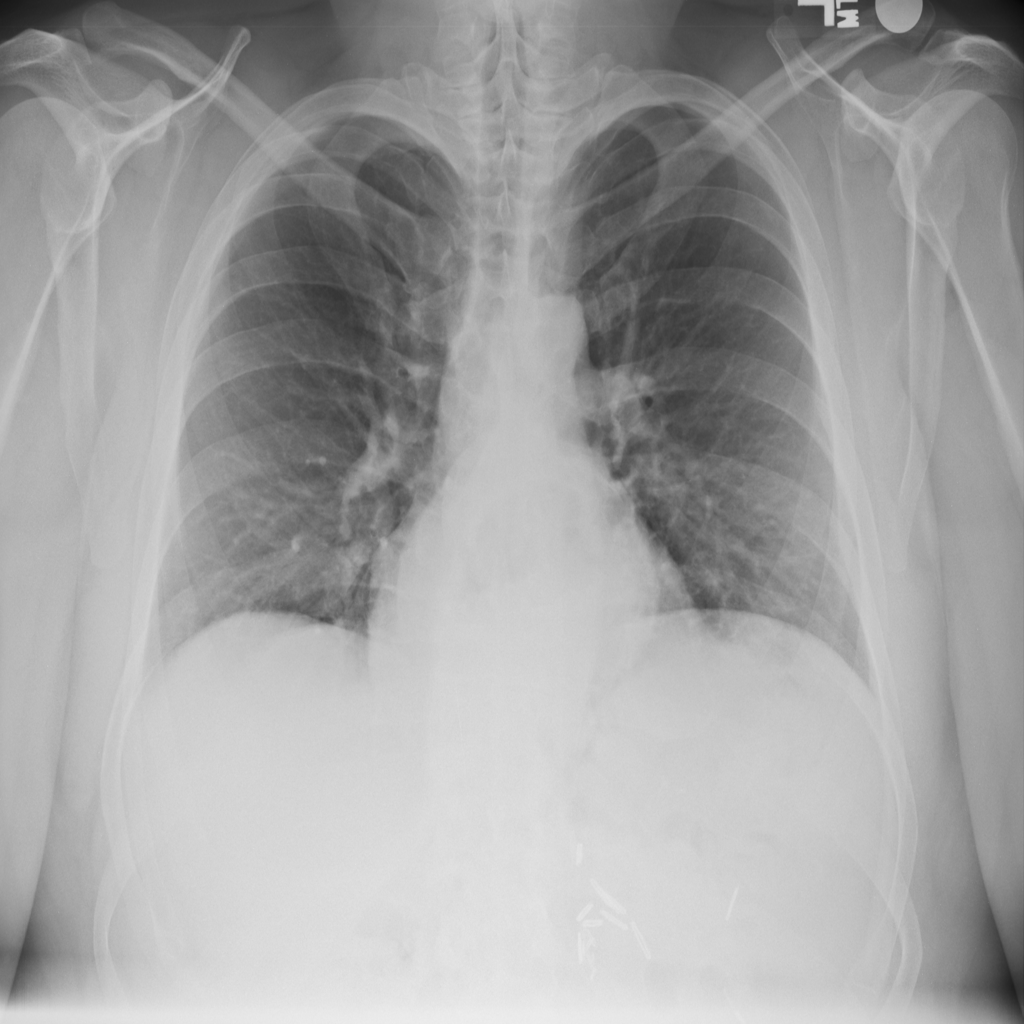

PAT-C048 · IMG-000Hernia

PAT-C048 · IMG-000

PA